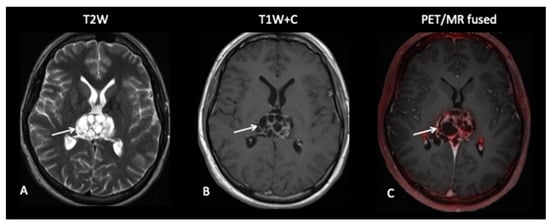

- Patient 10: Diagnosis

This 15-year-old female had a short-presenting history of recurrent headaches, vertigo, back ache and a band like numbness around the right breast and chest. She also complained of her legs “giving away”. MRI of the brain and spine revealed multiple lesions involving the brain with multiple drop spinal lesions occupying the spinal canal, compressing the spinal cord and nerve roots at all the levels (Figure 13), suggestive of a high-grade tumour. Surprisingly, the FCho PET–MRI showed that all the lesions in the brain and spine were choline non-avid, suggestive of a low-grade tumour, i.e., a low proliferative index, but a subsequent biopsy of the spinal lesion confirmed medulloblastoma.

Figure 13.

Spinal MRI (A,B) demonstrates extensive intraspinal-enhancing soft tissue in keeping with leptomeningeal metastatic disease (arrows point out the leptomeningeal disease). However, the FCho PET (C) did not demonstrate avidity of the leptomeningeal disease (arrows).